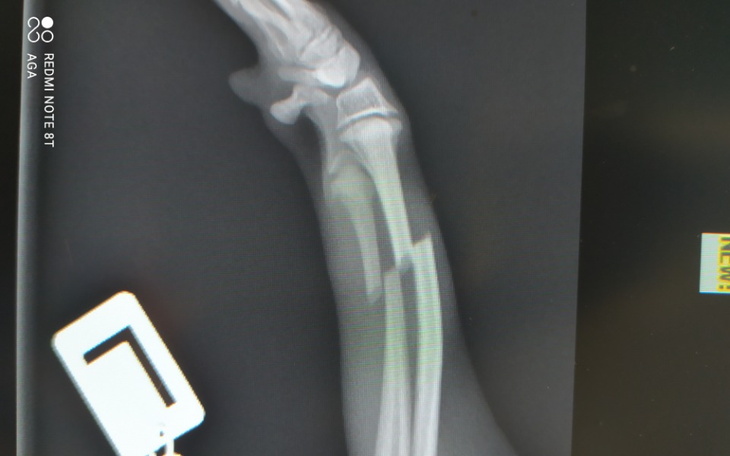

Nasz pies miał wypadek, w wyniku którego złamał dwie kości przedniej łapy. Operacja złamania jest bardzo kosztowna, a samo usztywnienie i podanie leków przeciwbólowych kosztowało nas prawie pół tysiąca. Sam koszt operacji to 3500zł plus późniejsze koszty rehabilitacji, które pozwolą psu na powrót do normalności i ponowne przyzwyczajenie się do używania złamanej łapy.